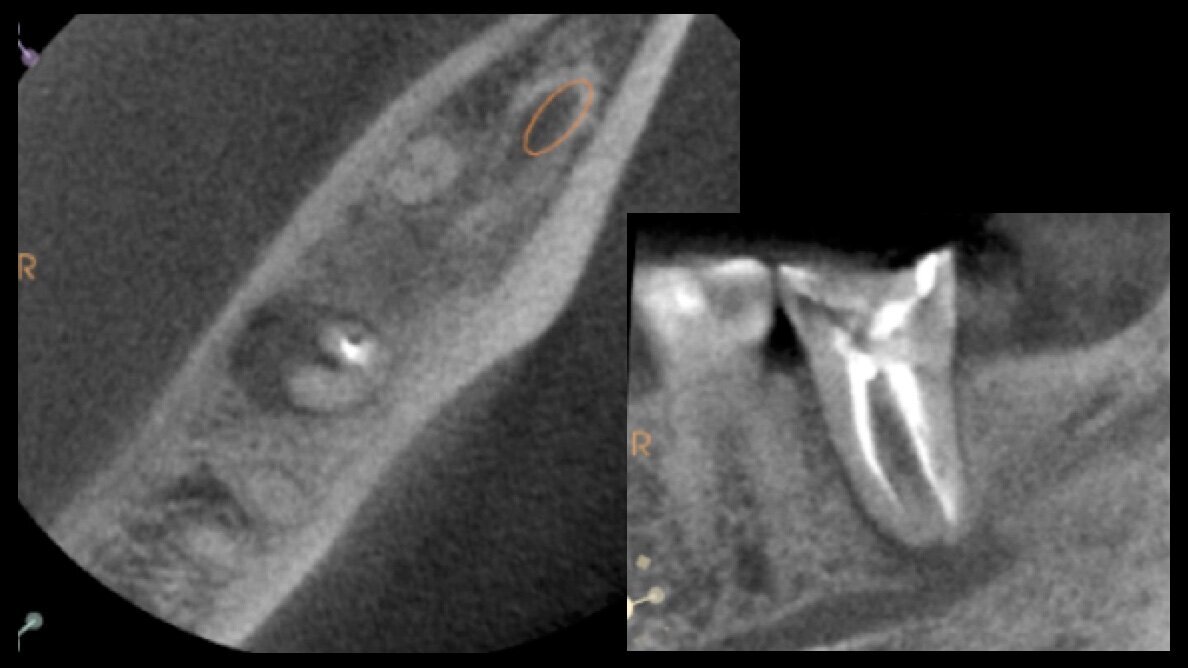

Figuras 1 y 2. Tomografía cone beam del diente 37 y Radiografía periapical del diente 37.

Estos PR (Figuras 1, 2) fueron incorporados en nuestra práctica, creando una técnica de reimplante intencional avanzada, que hemos llamado: Reimplante Intencional Digital.